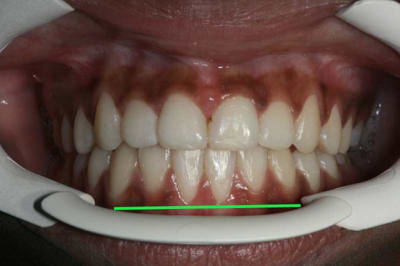

Voici un cas de béance associé à un Pb. paro sur 31/41

04/03/2010 à 15h26

il reste quand m un état imparfait

voici l'état de la gencive en fin de TTT. ORTHO